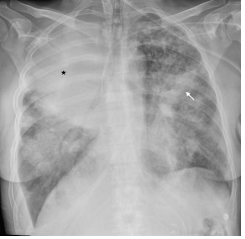

Figure 2: Chest X-ray taken on Day 17, two days after intubation and on mechanical ventilation. Right upper lobe shows signs of atelectasis and consolidation (asterisk). In the left lung there are extensive patchy infiltrates with partial atelectasis (arrow).

A follow up chest x-ray on Day 17 showed increasing atelectasis (Figure 2) and repeated bronchoscopies the next days turned out to be of utmost importance. Her airways were completely covered with a continuous membranous pale layer, starting along the tracheal tube, reaching down into the bronchial segments (3rd generation bronchi) narrowing the inner lumen significantly. The membranes completely covered the entrance to the left upper lobe, while the right upper lobe bronchus was left with a small remaining lumen (Figure 3).